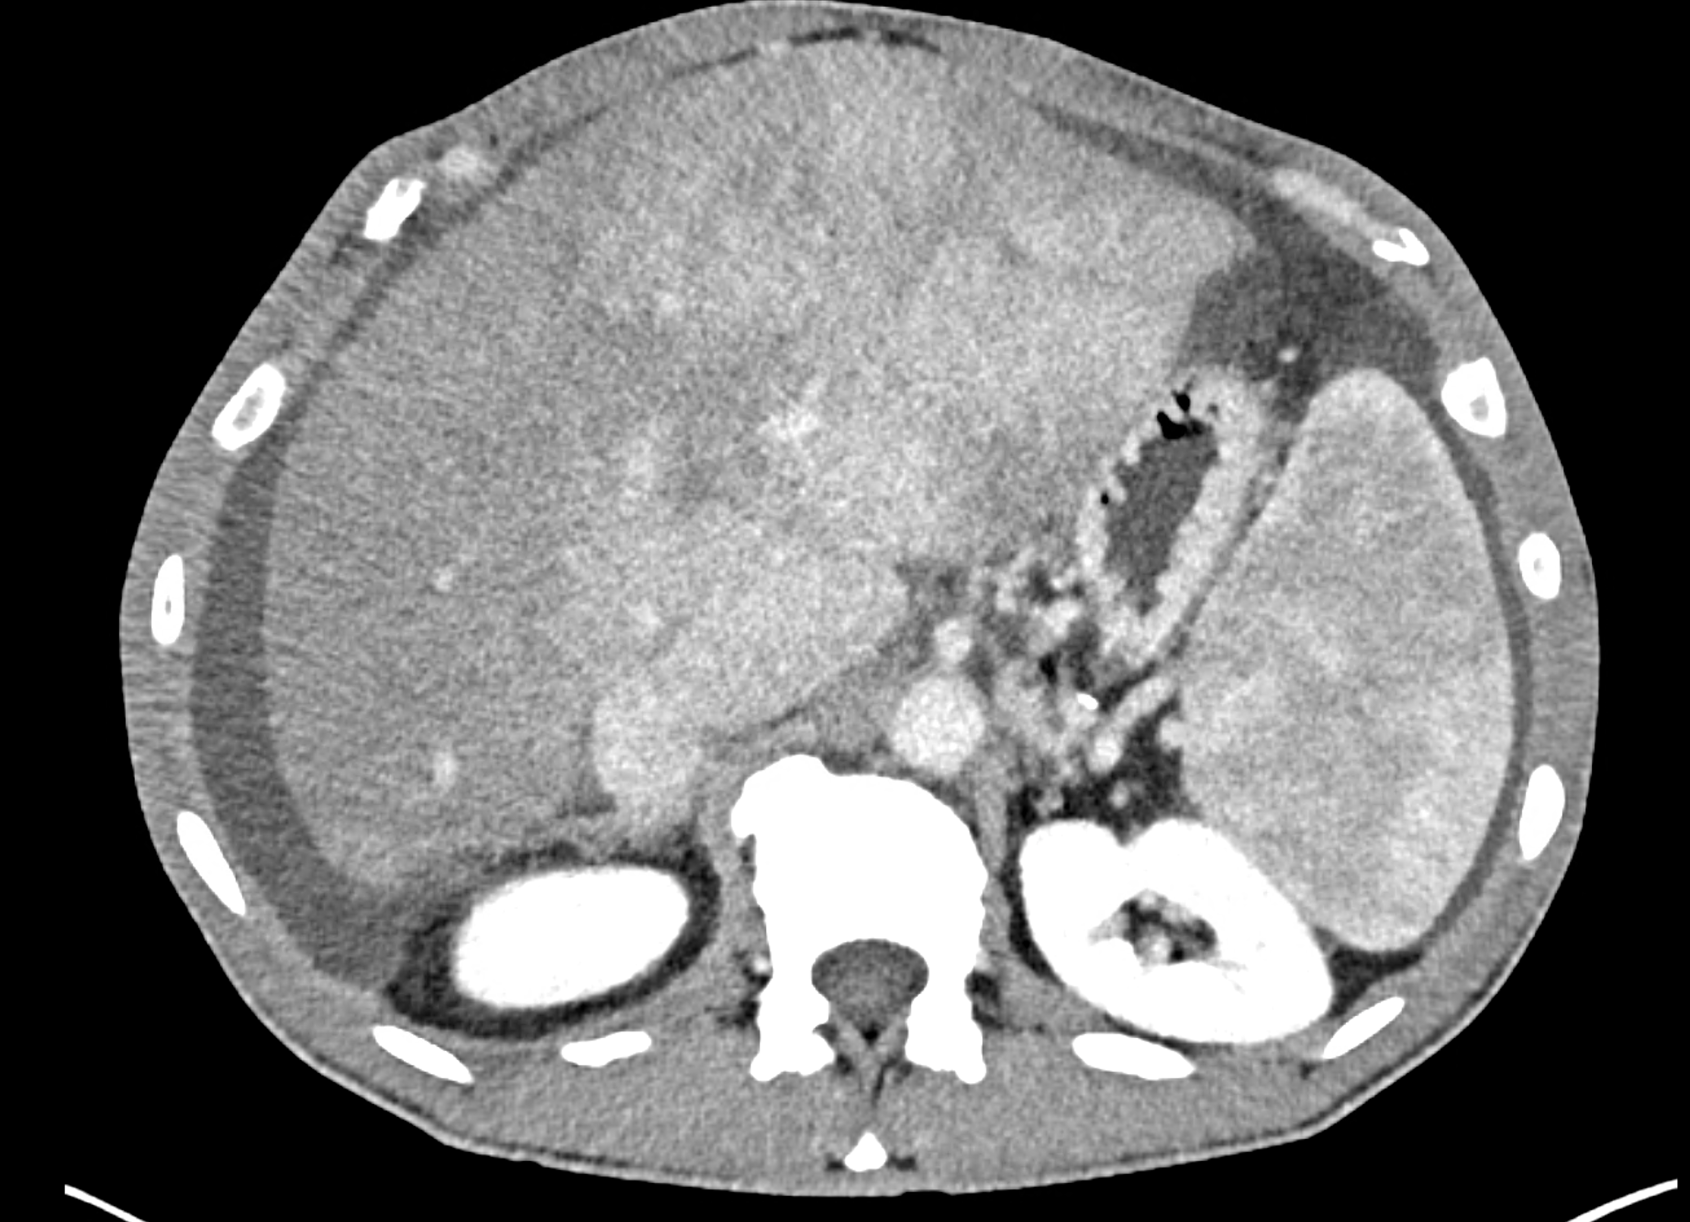

In CT images, BCS manifests as non-homogeneous enhancement of liver tissue in the arterial and especially in the portal phase, although in the portal phase may be increased, especially in the caudate lobe and left lobe, which are often hypertrophic (the hypertrophy and the enhancement is caused due to the possibility of the venous drainage directly into the inferior vena cava through the direct caudate veins), in contrast to the reduction in the right lobe. The portal vein is free, whereas even in the late phase, the hepatic veins and their contrast filling are not visible. Thrombotic occluded veins are hypodense.

A patient in his sixties with a Leiden mutation of factor V and a heterozygous prothrombin mutation presents with abdominal pain. Ultrasound examination reveals ascites and enlargement of the liver.There is enlargement of the liver, particularly the left lobe and caudate lobe. The hepatic veins are centrally filled with contrast medium due to reflux at the confluence with the inferior vena cava, and their radicular parts are thrombosed. There is typical chronic liver remodelling and the formation of centrifugal collateral circulation, including esophageal varices, and ascites is present in the abdominal cavity.

the axial images in the arterial, and the portal phases